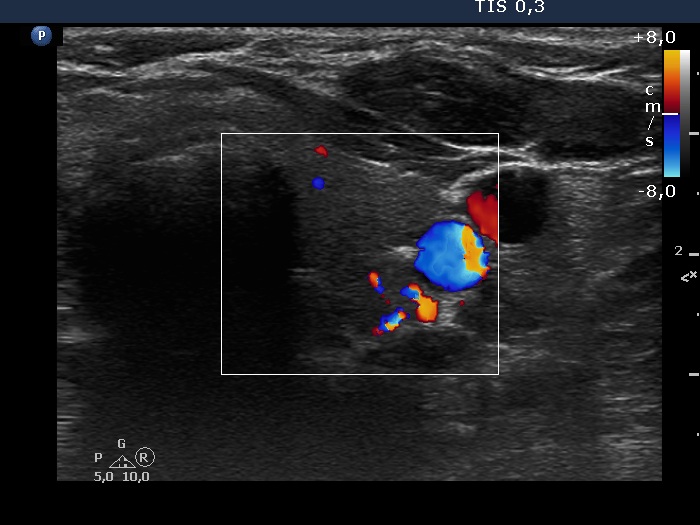

Discrete lesion or nodule in Hashimoto's thyroiditis - case 3 (1447) (ultrasonographic picture 6)

Right lobe, longitudinal scan

Left lobe, transverse view, color Doppler mode. The vascularization is not specific.